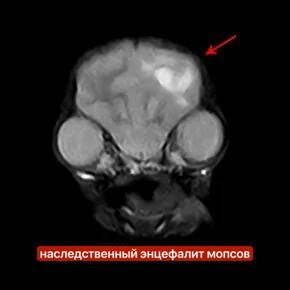

НАСЛЕДСТВЕННЫЙ ЭНЦЕФАЛИТ МОПСОВ (НЭМ)

❗️ Это тяжелое, прогрессирующее и, как правило, фатальное неврологическое заболевание, вызванное генетической предрасположенностью.

➡️ МРТ (магнитно-резонансная томография) головного мозга, которая выявляет очаги воспаления и некроза (отмирания тканей)